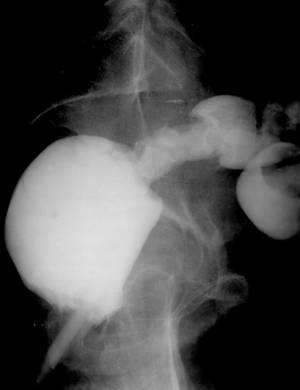

Fig. 47 – Colita ulcerativa

Fig. 48 – Colita ulcerativa complicata cu fistula externa

3. Rectocolita ulcero-hemoragica

a) stadiul I sau faza edematoasa consta in:

c) stadiul scleros:

- retractia segmentelor interesate;

- aglutinarea anselor (de regula ultima ansa ileala este acolata la cec);

- calcificari in ganglionii mezenterici.